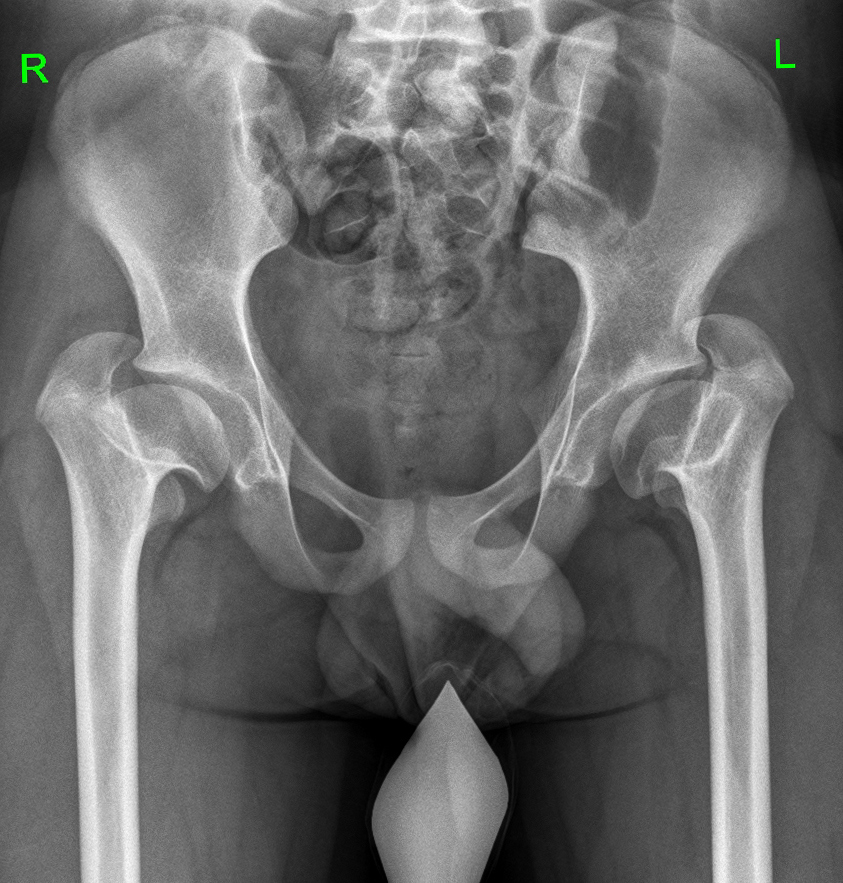

В нормальном тазобедренном суставе численно большим показателем из перечисленных является LTA. При выраженной гипертрофии большого вертела величина ATD принимала отрицательные значения, а показатель TTD становился больше LTA. Как видно на графике, это было характерно для подростков при сформировавшейся к окончанию роста деформации (рис. 9).

Рис. 9. Рентгенограмма пациента Б., 13 лет. Диагноз: «Состояние после консервативного лечения врожденного подвывиха бедра с двух сторон — последствия асептического некроза головки и шейки бедренной кости, высокое положение большого вертела». Вертельно-тазовый конфликт обусловлен выраженными анатомическими нарушениями, которые сопровождаются характерной клинической картиной и болевым синдромом

У детей с показателем ATD 0 и менее положительный симптом Тренделенбурга обнаружен в 87 % случаев. В дальнейшем у этих пациентов отмечались и клинические признаки вертельно-тазового конфликта — боль при отведении, разгибании и ротации бедра. При сравнении показателя ATD в норме и при патологии выявлена закономерность его уменьшения в динамике с ростом ребенка в пораженных тазобедренных суставах (рис. 10).